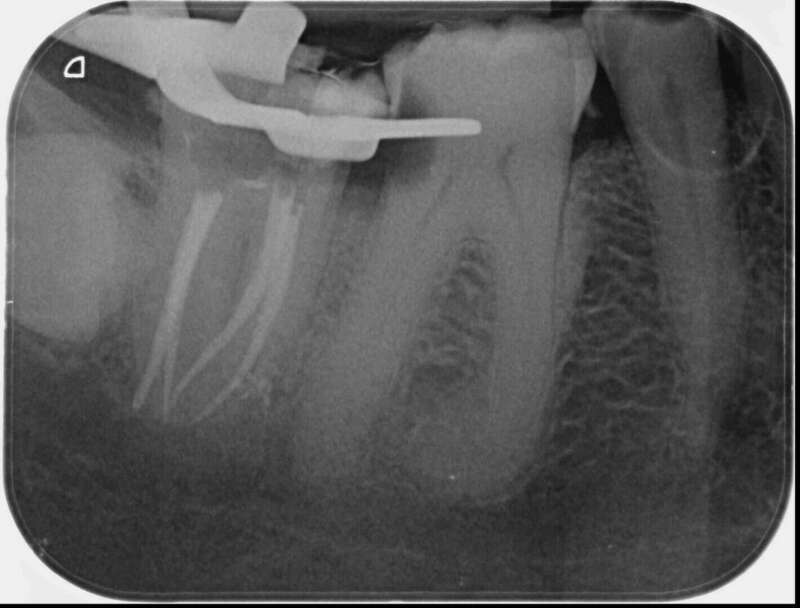

Avant

Après